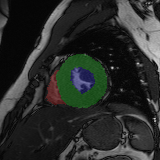

Refer to caption

Figure 2: Examples of tracking results using the proposed method (MPN-C). From left column to right: ED frame, ES frame, warped frame from ED, overlay of ES frame and the warped mask, and estimated motion field using HSV color coding. The color coding wheel legend indicates the motion directions.